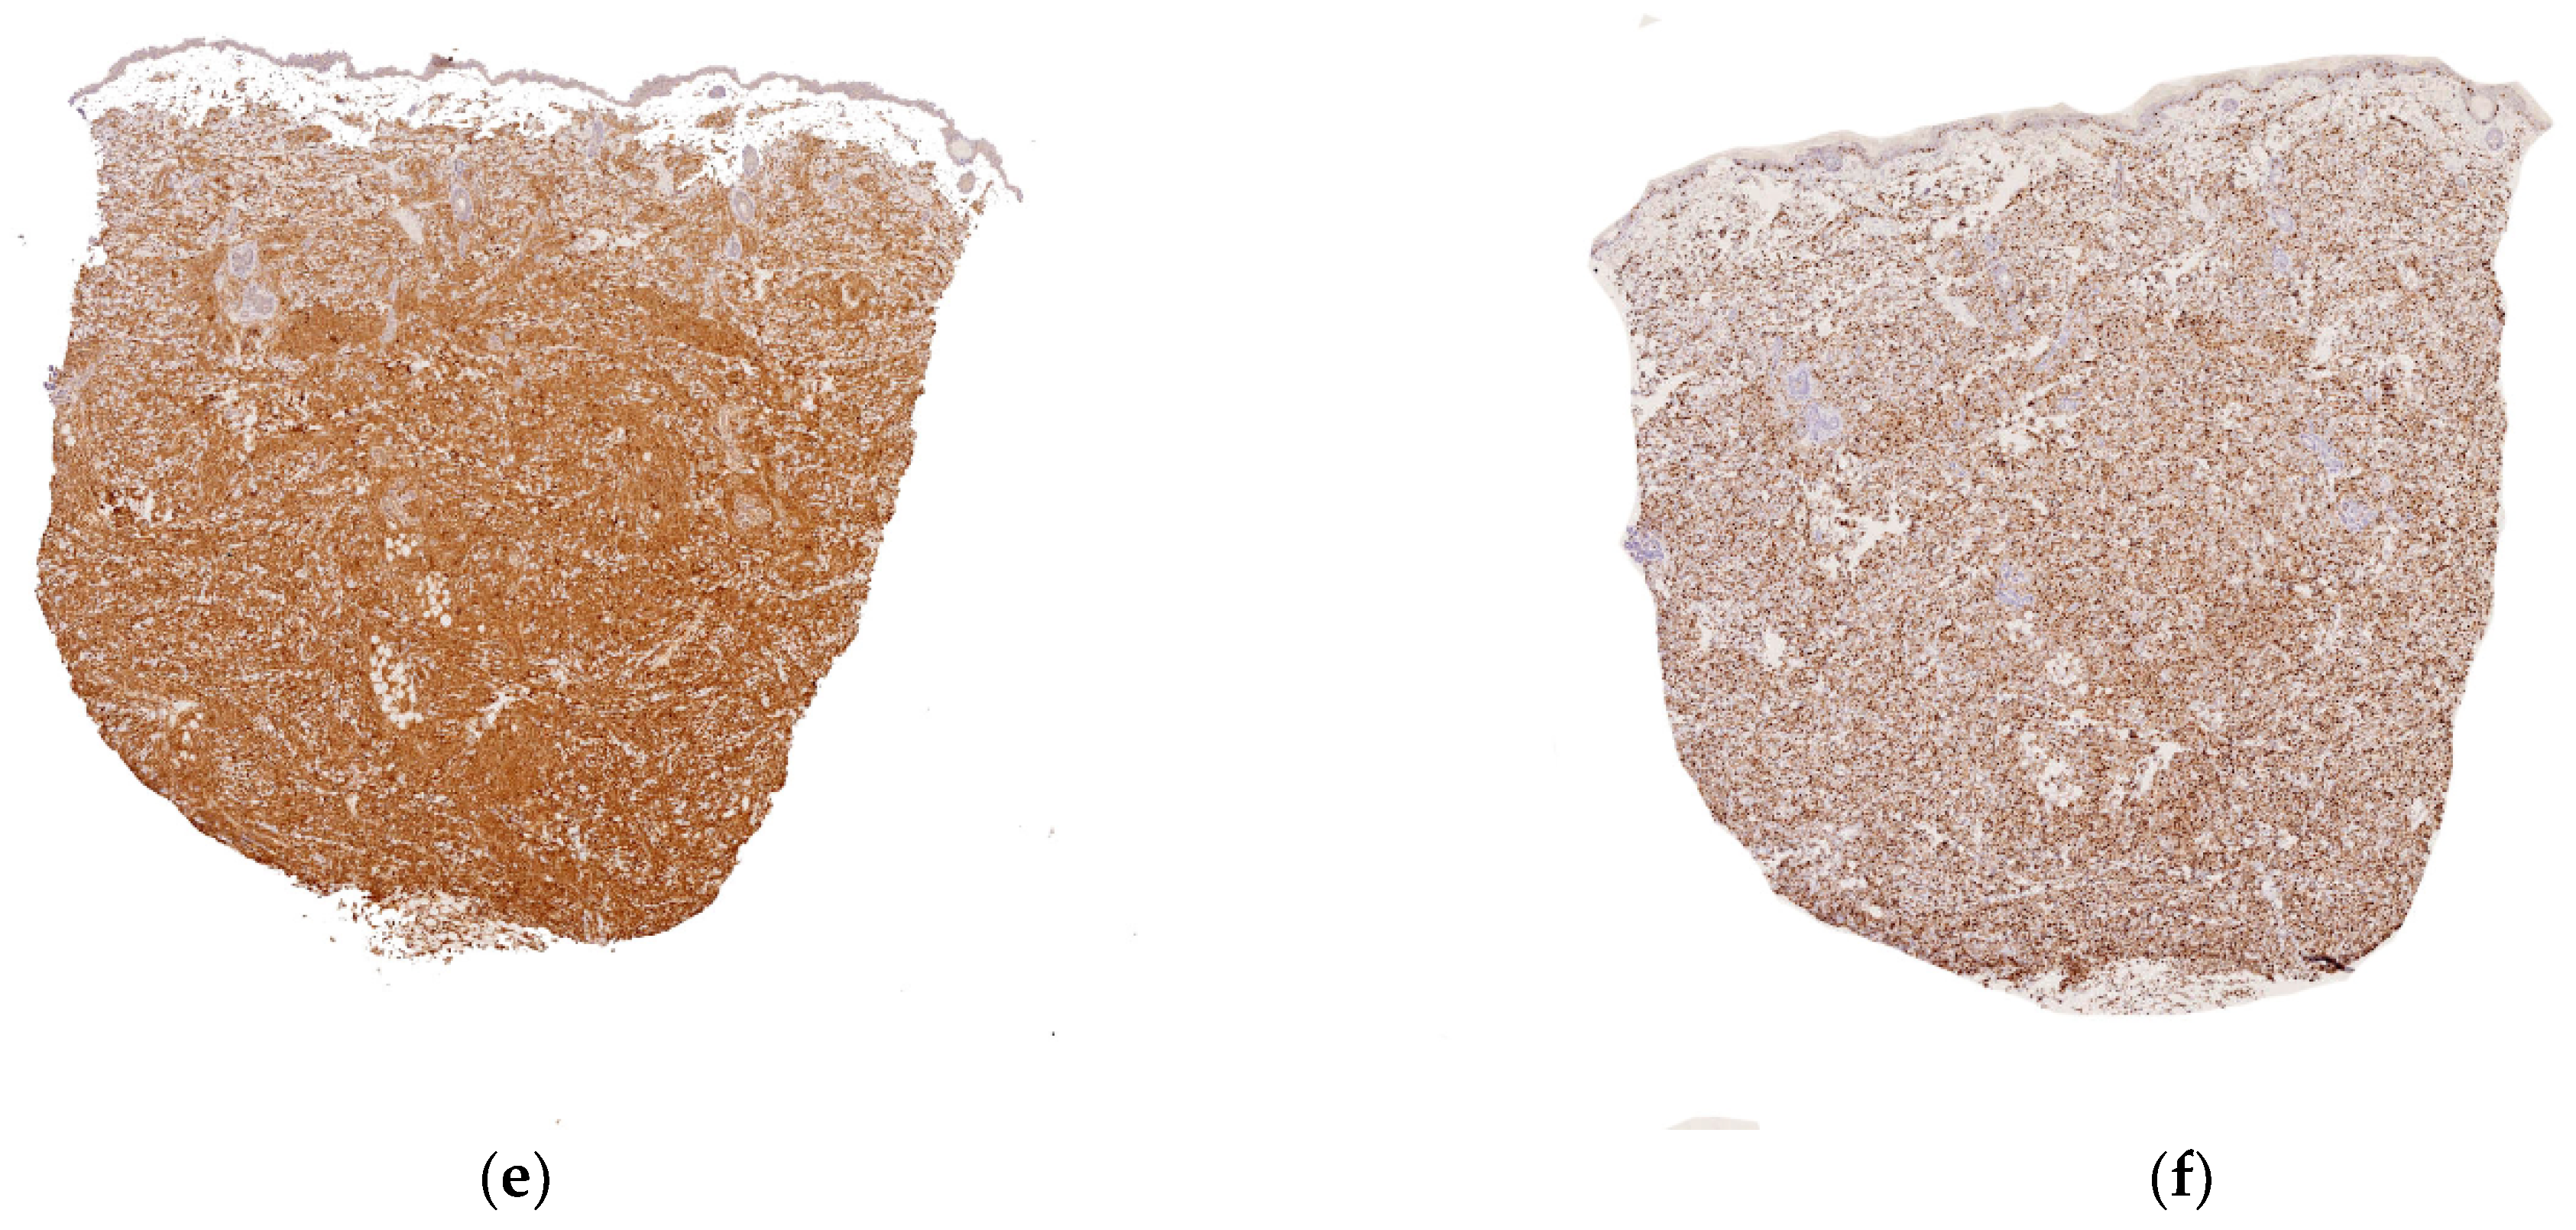

Figure 4.

Congenital leukemia cutis: (a) blueberry muffin rash; (b) 4× dense dermal infiltration separated from the epidermis by a grenz-zone; (c) 10× medium-sized blastic cells arranged in single-file between collagen bundles and with a peri-vascular and peri-adnexal arrangement as well; (d) 25× apoptotic cells and mitotic figures; (e) CD68 intense positivity; (f) Ki67 immunostaining: almost 100% of nuclei are positive.

Histology

In most cases, the diagnosis is straightforward. A dense dermal infiltrate is separated from the epidermis by a “grenz zone” and extends into the subcutaneous tissue with a peri-vascular and peri-appendageal arrangement. Cells are arranged in single file between the collagen bundles. They are medium-sized, with a high nuclear-cytoplasmic ratio, nuclear debris (apoptosis), and mitotic figures (Figure 4b–h). A good clue is the very high proportion of tumor cells, and almost no reactive inflammatory cells, in the infiltrate. CD68, lysozyme, and myeloperoxidase are the most sensitive immunohistochemical markers for detecting monoblasts (acute monocytic leukemia 5) or myelomonoblasts (acute monocytic leukemia 4), which account for the vast majority of leukemias at this age. In most cases, 90 to 100% of the cells are positive for KI67. Importantly, these immature monoblasts may lack CD163.